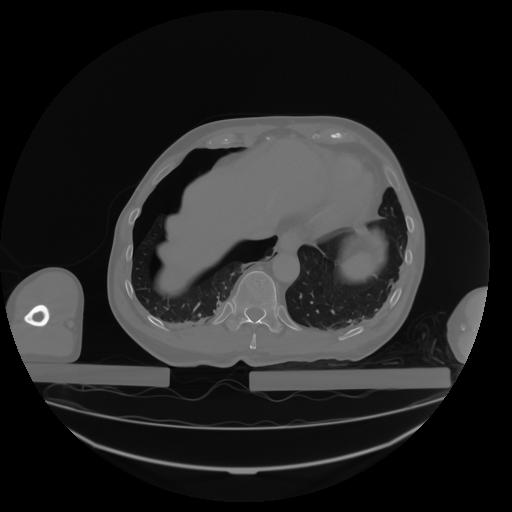

27 CUERPO,CE,Axial,3.0,CUERPO,,